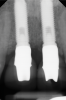

Fig 2. Baseline periapical x-ray.

Figure 2

A 46-year-old systemically and periodontally healthy woman presented to the Graduate Periodontics Clinic at the University of Michigan School of Dentistry with the chief complaint of poor esthetics of her smile due to two dental implants (Nos. 8 and 9) showing their metal components (Figure 1). The patient reported that the implants had been placed 15 to 20 years previously after an accident. Clinical examination revealed that the implants had probing depths within 3 mm (facial probing depth of 3-2-3 mm for implant No. 8 and 2-2-2 mm for implant No. 9), no bleeding on probing, and no suppuration; the implants were therefore diagnosed as healthy (Figure 1 and Figure 2). The papilla between the two implants was deficient on the buccal aspect. The implants were buccally positioned, and a substantial lack of soft-tissue volume was noted.